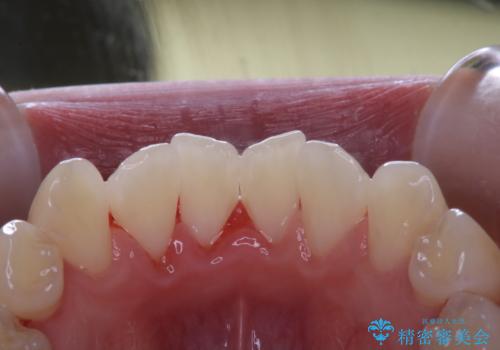

30代男性 PMTCで歯石取り